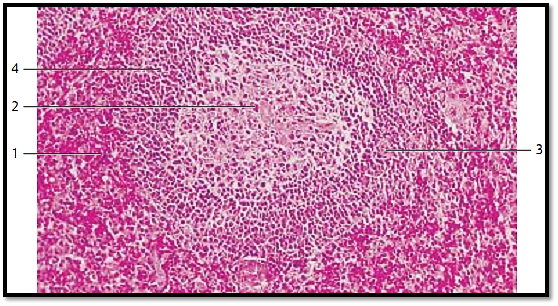

The parenchyme of the spleen consists of the white pulp (= all lymphoreticular arterial sheaths, T-cell region ) and the red pulp 1 . This figure shows white pulp as part of a round lymph follicle (folliculus lymphaticus splenicus ). It features a prominent germinal center 2 . The branches of the trabecular artery run through the follicle and are now called follicular artery 3 or central artery. There are usually two to three follicular arteries. They traverse the arterial sheaths eccentrically, especially when secondary follicles with germinal centers (B-cell regions) are present, as is the case here. A barrier of small lymphocytes surrounds the germinal center 2 , which is called corona or mantle zone 4 . The area around the splenic follicle represents re d pulp 1.

1 Splenic red pulp

2 Germinal center of a spleen follicle

3 Follicular (central) artery

4 Corona or mantle zone

Stain: alum hematoxylin-eosin; magnification: × 100